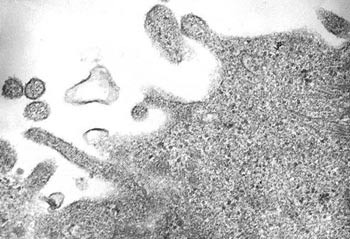

Indirekte immunflourescens ved hjelp av polyvalente kaninantistoffer som er utviklet ved vår avdeling ser ut til å gi gode resultater på cellekultur (fig 2). Anvendt direkte på prøvemateriale, er sensitiviteten ca. 50 % sammenliknet med resultatene ved polymerasekjedereaksjon. Bruken av metoden direkte på prøvemateriale fra nasopharynx har vært lovende og vil bli validert for klinisk bruk. Viruset lar seg også påvise ved hjelp av elektronmikroskopi fra cellekulturer (fig 3). Sekvensering av stammer isolert i Trondheim viser at utbruddet i 2002 – 03 ble forårsaket av genotype A1 mens stammer fra vintersesongen 2004 – 05 tilhører genotype B2. Vi har også observert at B2-stammene av og til gav cytopatogen effekt i noen av våre cellelinjer (syncytiedanning), mens stammer tilhørende genotype A1 ikke gav synlige celleforandringer i det hele tatt.